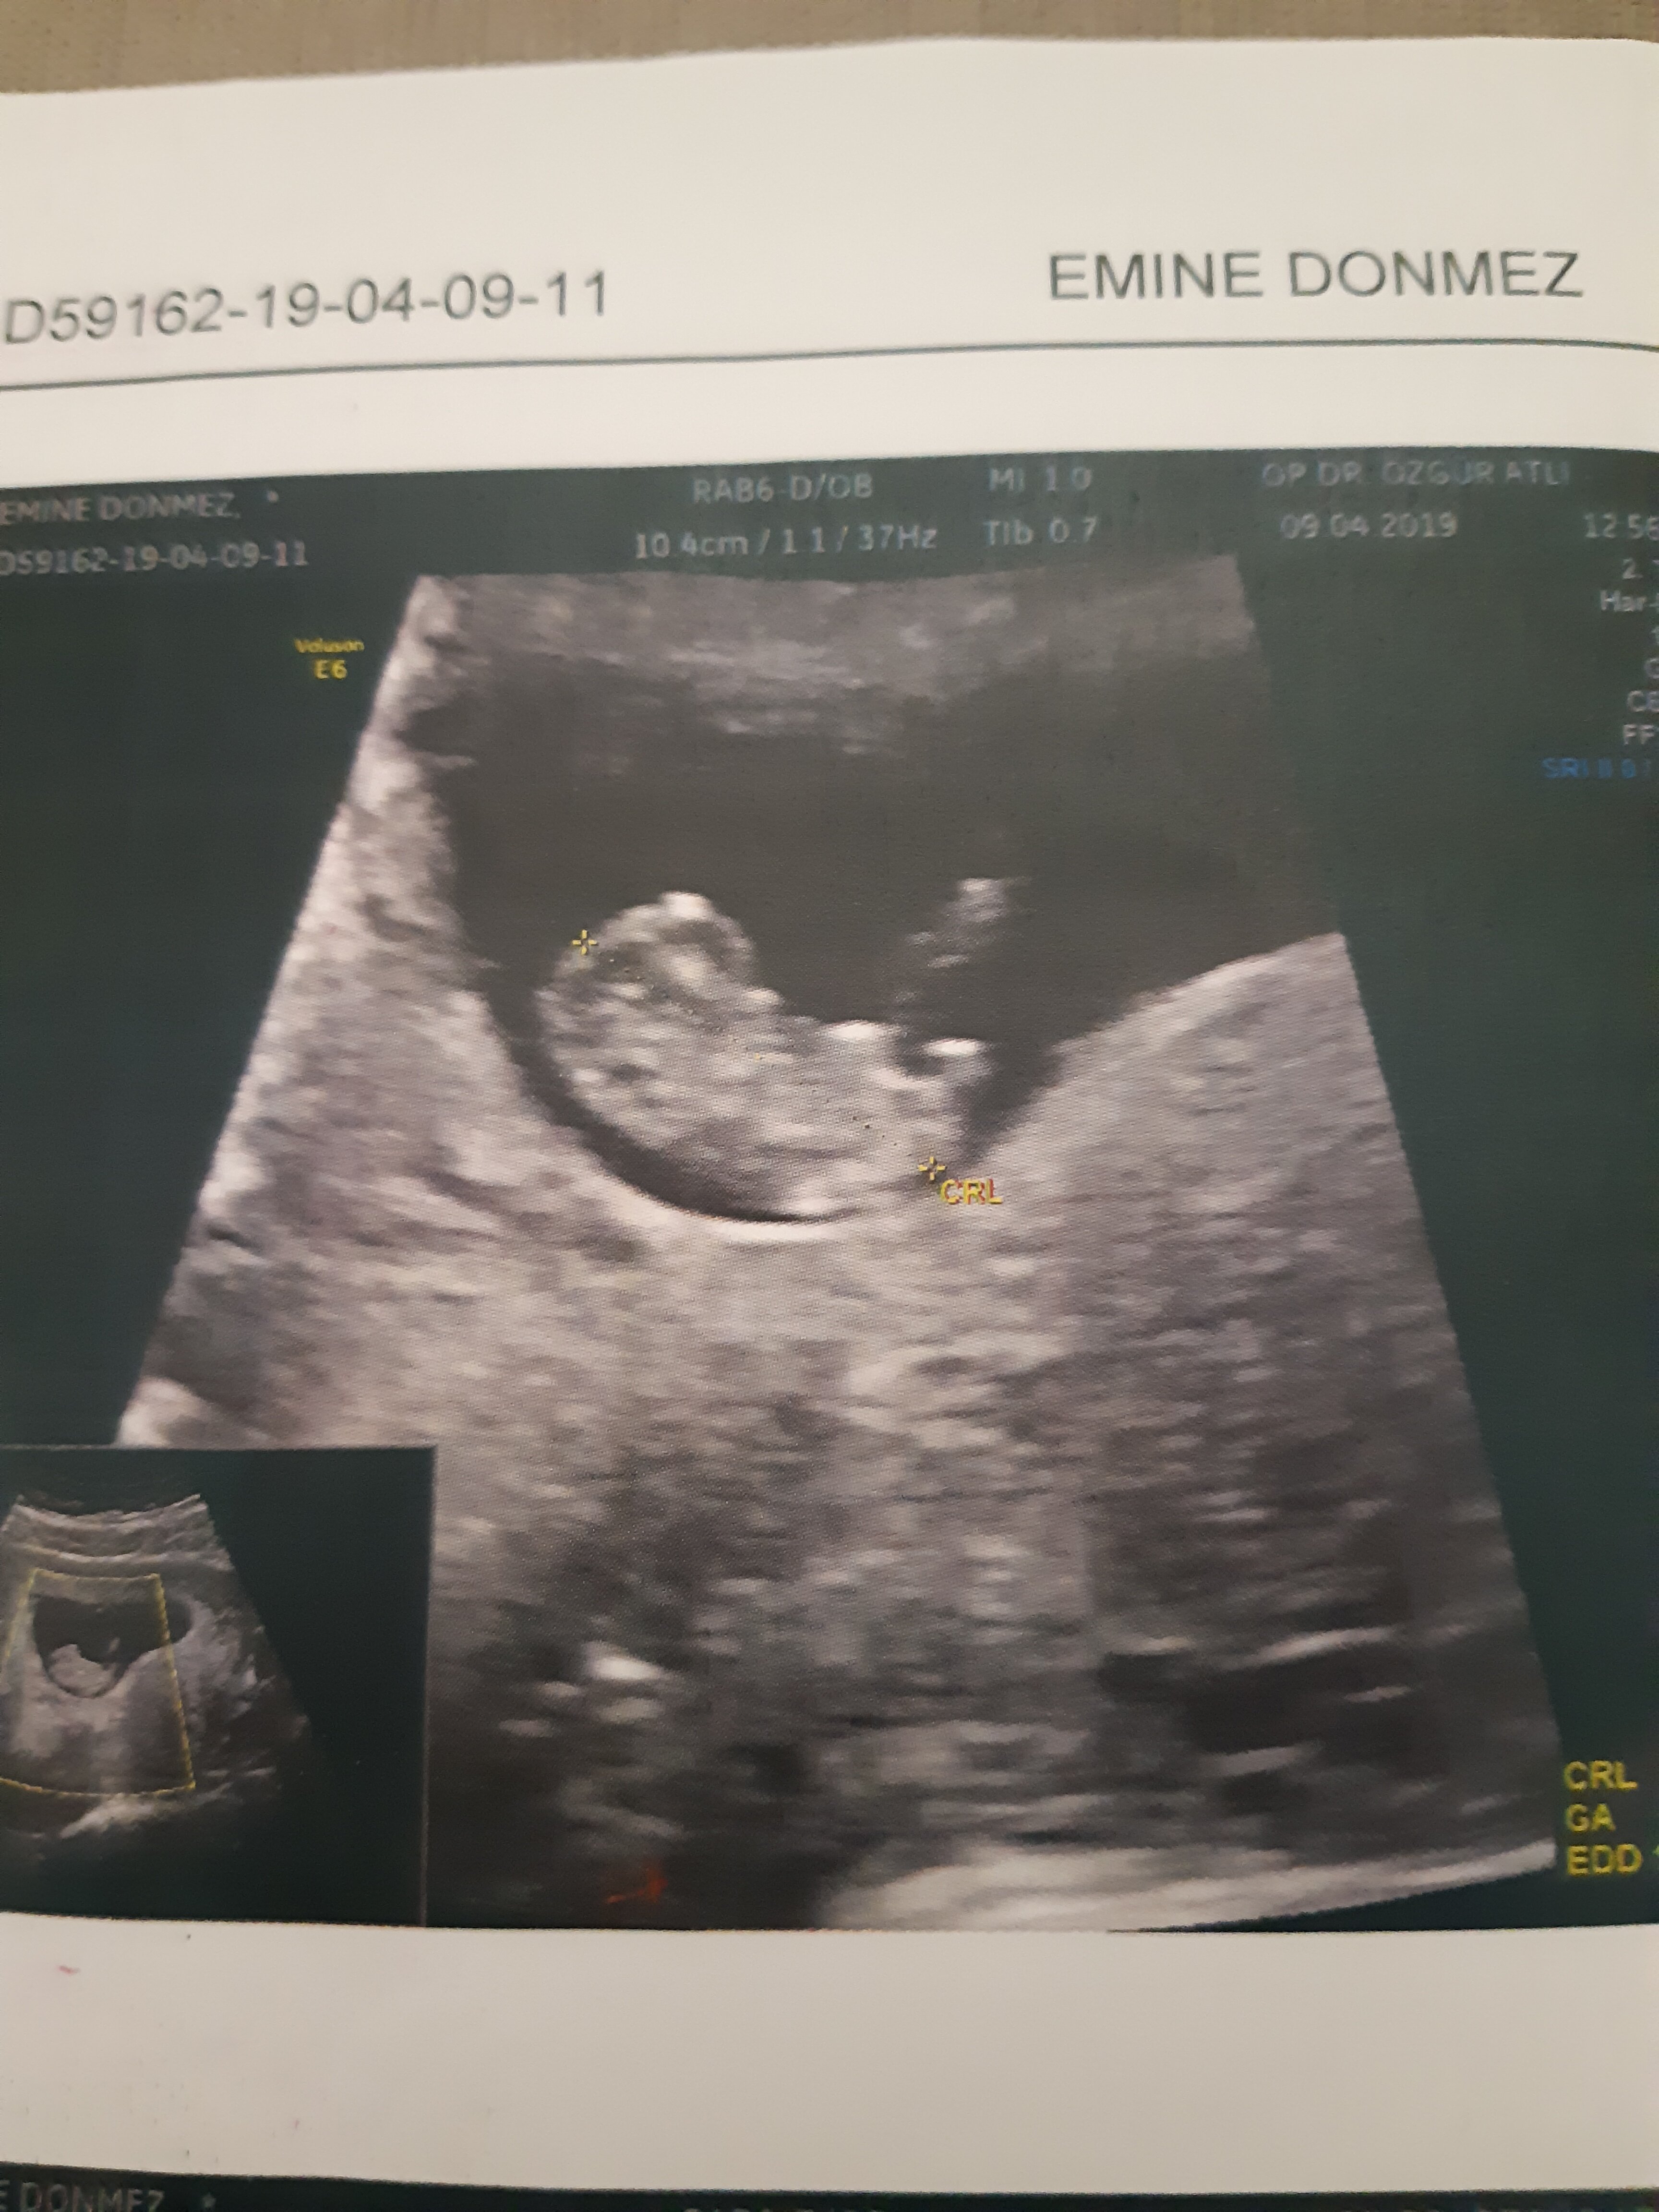

Benm kendi doktorum olmadğı içn 12. hftada farklı bir doktora ikili test yaptrmştm ve cinsiyetinin kız olduğunu söylemşti

ama 16. haftada tekrar gittiğimde kendi doktorum erkek olduğunu söyledi sizce nedir? doğru sonuç için detaylıyı mı beklemeliyim???

Belittiğiniz haftalarda cinsiyet tahmininde yanılmalar olabilir. Gebeliğin 17-18-20 . haftalarında bebeğinizin cinsiyetini net olarak öğrenebilirsiniz.